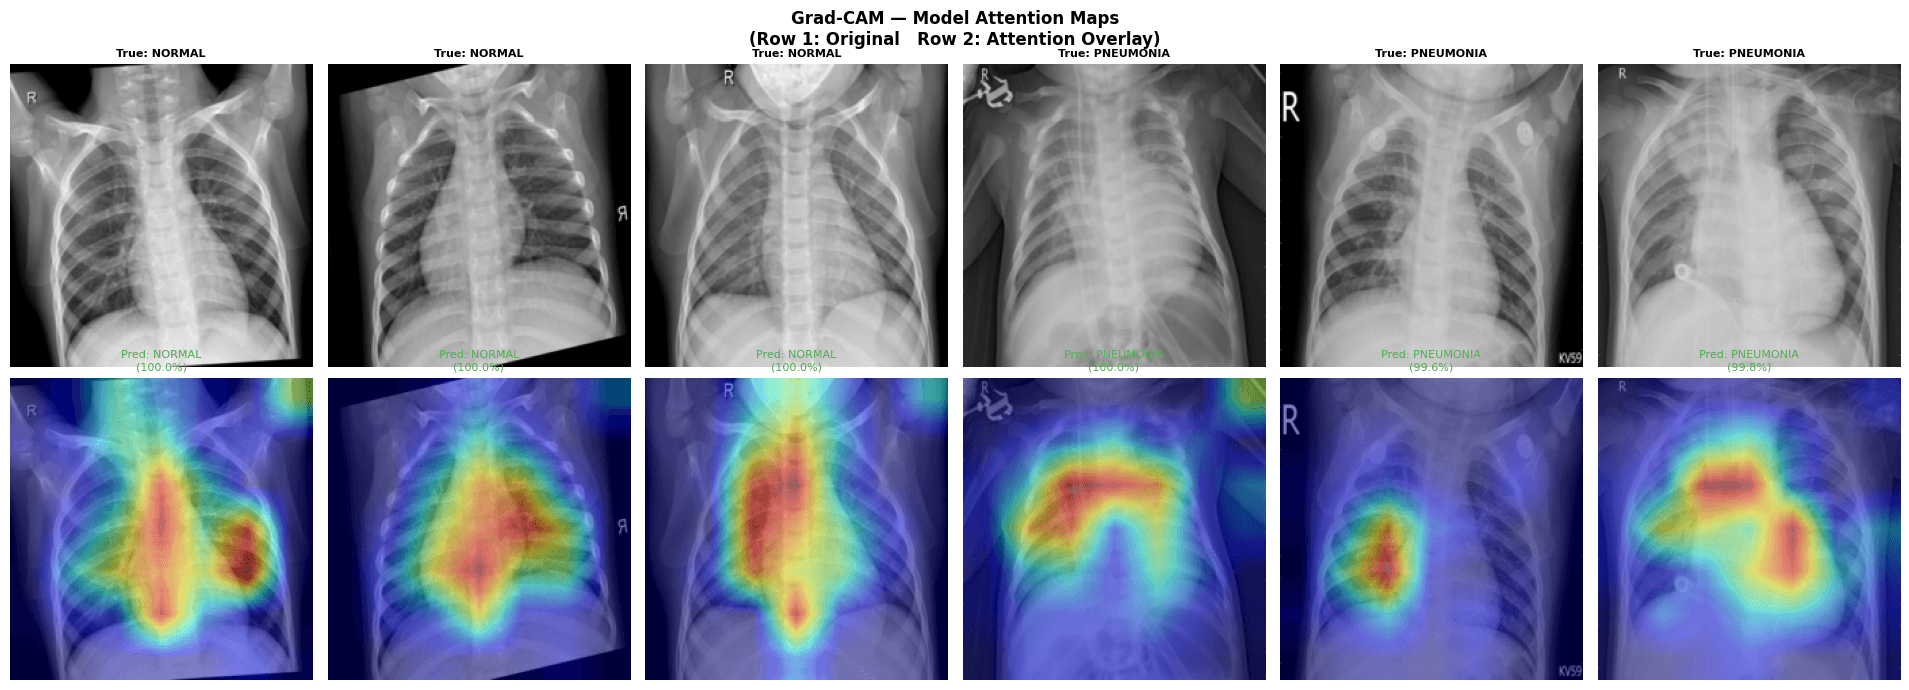

100% specificity on normal cases (zero false positives). Grad-CAM attention maps available to show which regions the model used for each prediction.

Interpretability

Grad-CAM attention maps show which regions of the X-ray the model used for each prediction — building trust and supporting clinician review.

- Grad-CAM attention maps for interpretable, auditable predictions